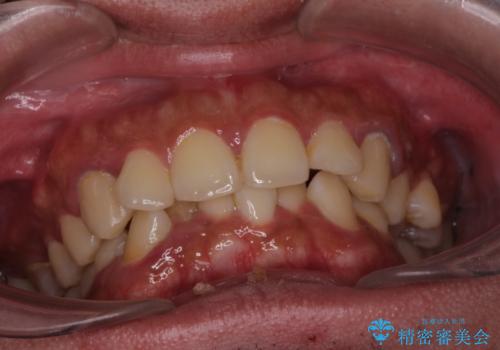

がたつきが気になる。インビザラインでスッキリ。

- 奥歯の噛み合わせは特に問題ないため臼歯を特に大きく動かす事はなく。

歯と歯の間を削る(ディスキング)、拡大を行いマウスピースで矯正を行いました。

がたつきもなくなりスッキリした歯並びになりました。